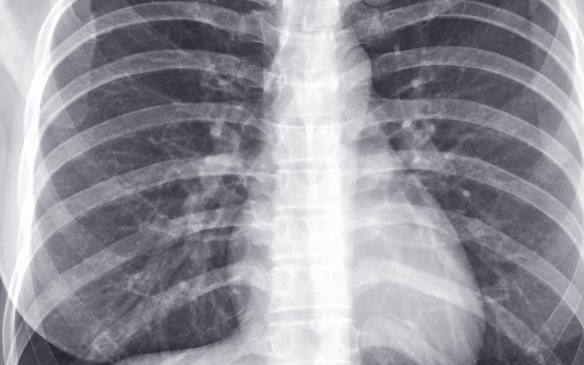

World Radiography Day is observed annually on November 8. It commemorates the discovery of x-radiation by Wilhelm Conrad Roentgen in 1895. This day marks the importance of radiographers in healthcare. It also aims to raise awareness about radiographic therapy. The theme for 2024 is ‘Radiographers – Seeing the Unseen’.

Radiographers play important role in modern healthcare. They operate imaging equipment for diagnostics and treatment. Their expertise ensures accurate imaging, which is vital for patient care. This day acknowledges their contributions and promotes the profession. It also marks their responsibility in safeguarding patient health.

Roentgen’s discovery revolutionised medical diagnostics. It allowed healthcare professionals to view internal structures without surgery. This innovation changed how conditions are diagnosed and treated. Radiography has since evolved, incorporating advanced technology and techniques. The impact of this discovery continues to be felt in healthcare today.

3. Radiographic Therapy: Radiographic therapy is a diagnostic tool in healthcare. It utilises x-rays to view internal structures. This method aids in accurate diagnosis and treatment planning. It is essential for modern medical practices.